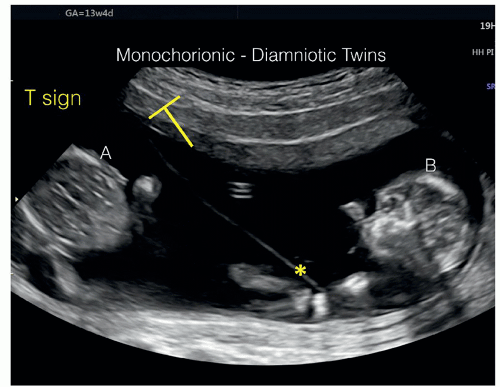

T Sign In Twins - They have separate hearts but share other organs.

Developing both a feeding and sleeping schedule for baby twins can be a lifesaver for their parents. Monochorionic Diamniotic Pregnancy Radiology Case Radiopaedia Org